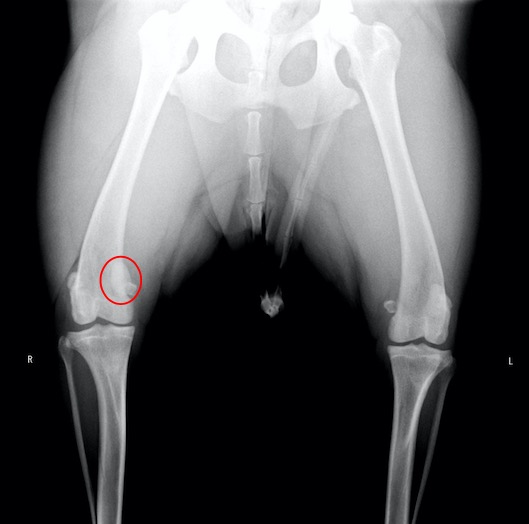

右の膝蓋骨が内方に脱臼しています。